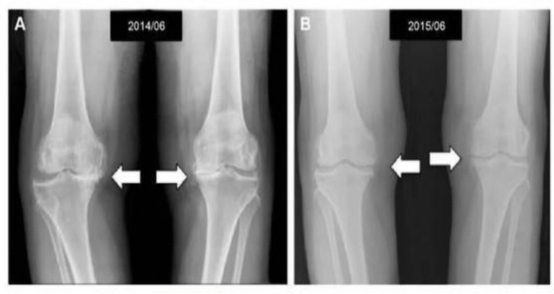

• 干细胞治疗膝关节病变的影像学改变:

4、关节变形:在治疗后3个月开始,膝关节畸形开始逐步好转。